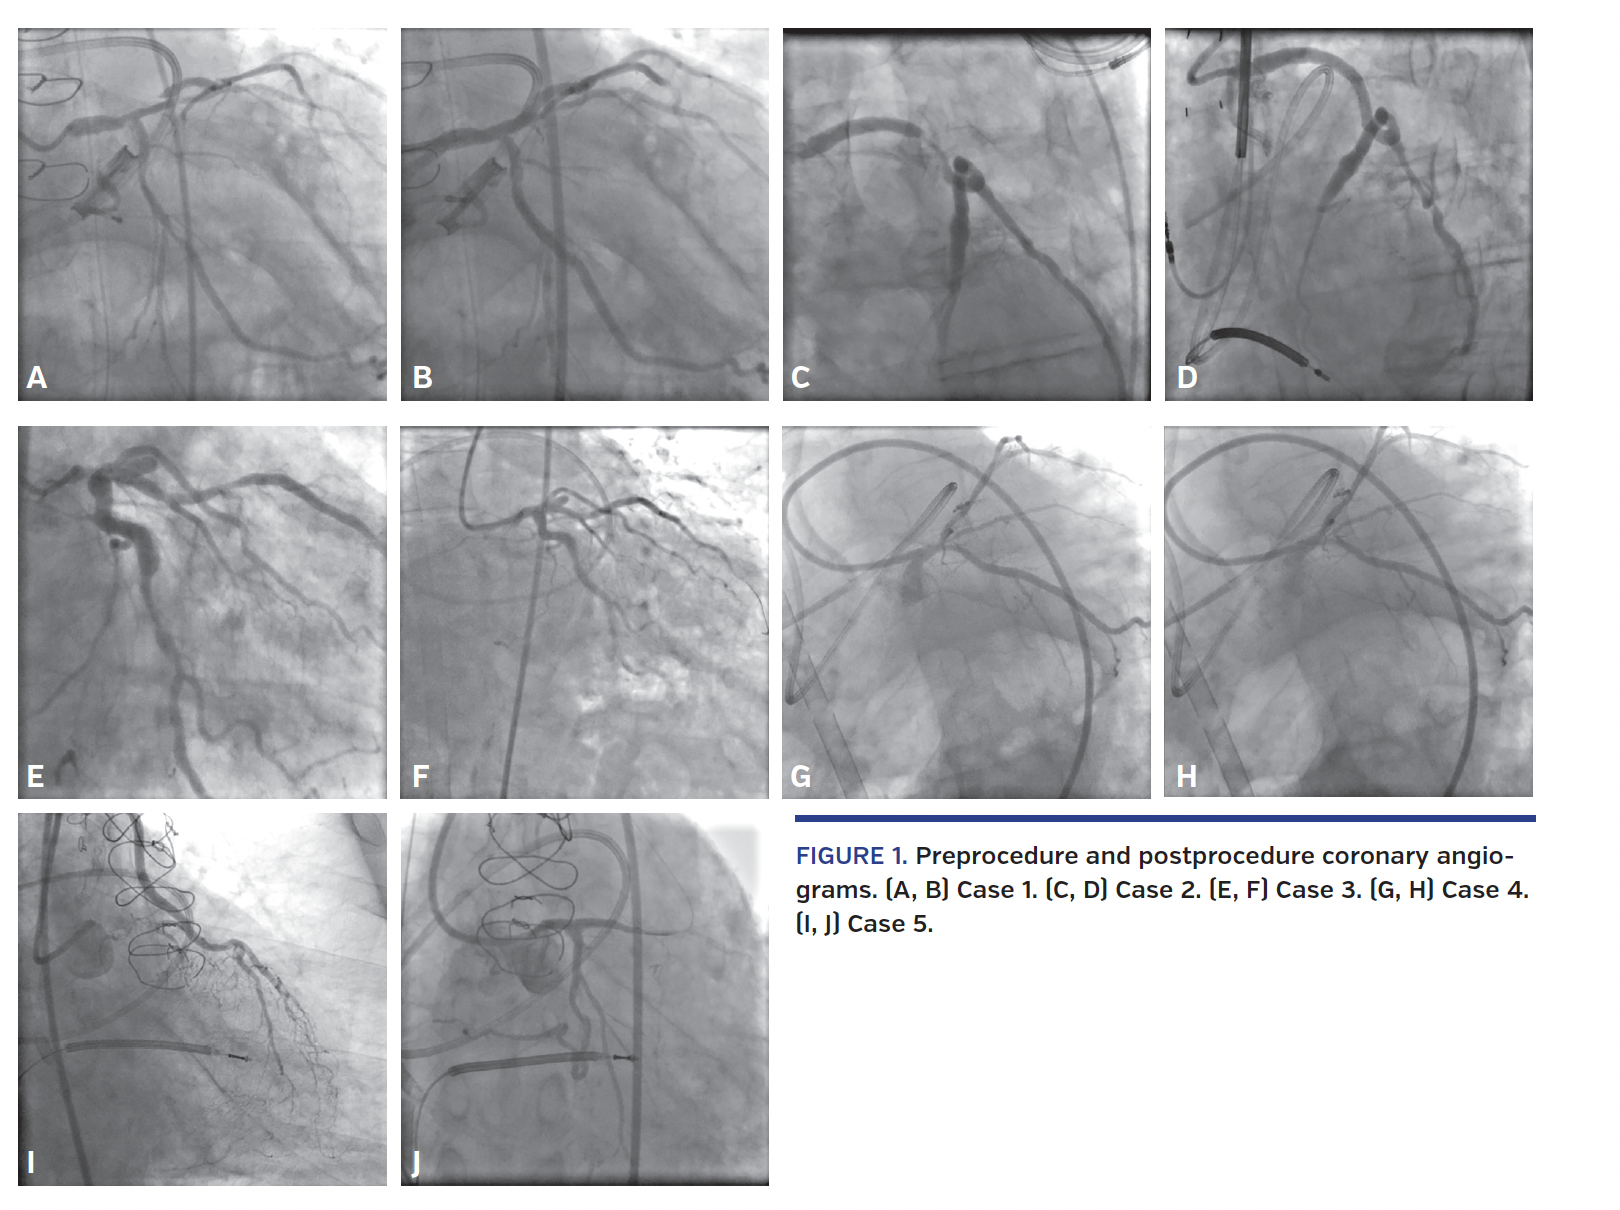

Five patients underwent elective high-risk PCI with ECMO support during the study period. Baseline clinical characteristics are shown in Table 1. Mean age was 66.8 ± 8.6 years (range, 55-76 years) and all patients were men. The mean ejection fraction (EF) was 26.6 ± 18.0%. Most procedures were unprotected left main PCIs (Table 2). One case (patient #5) was a chronic total occlusion (CTO) intervention through the last remaining conduit. The indication for PCI was left ventricular (LV) systolic dysfunction in 4 patients, and non-ST elevation MI in 1 patient. The procedure was done with general anesthesia in 2 patients, conscious sedation in 2 patients, and monitored anesthesia care in 1 patient. Mechanical ventilation was used in the 2 general anesthesia cases. The anesthetic method was decided by the primary operator and anesthesiology was based on each patient’s clinical status and anticipated length of procedure. A Swan Ganz catheter was utilized at the discretion of the primary operator in 4 cases. Mean procedure duration was 217 ± 157 minutes. All PCIs were angiographically successful (Figure 1). No sustained ventricular arrhythmias occurred during the procedures. Mean number of drug-eluting stents implanted per patient was 2.4 ± 1.2, with a mean stent length of 19.2 ± 3.9 mm. Mean fluoroscopy time was 38.4 ± 34.6 minutes and air kerma radiation dose was 1.69 ± 0.97 Gray. Mean residual SYNTAX score after PCI in patients without prior coronary artery bypass graft (CABG) surgery was 7.3 ± 5.5. One patient developed a left common femoral artery pseudoaneurysm at the ECMO arterial cannula insertion site and required surgical repair by vascular surgery. Two patients had groin hematomas (type 1 and 2 bleeding, respectively, according to the BARC criteria). Neither required blood transfusion or further intervention. Mean hemoglobin drop post procedure was 2.46 ± 1.45 g/dL. One patient had acute kidney injury without needing hemodialysis. There was no occurrence of limb ischemia or sepsis. The mean hospital stay after the procedure was 6.4 ± 2 days. VA-ECMO was successfully weaned in all cases; duration of ECMO was <24 hours in 4 cases and <48 hours in 1 case. There were no MACCEs during hospital stay and at 1-year follow-up. In all 4 patients with decreased LV systolic function, the EF improved at 1-year follow-up (mean increase, 24.3 ± 10.8%).